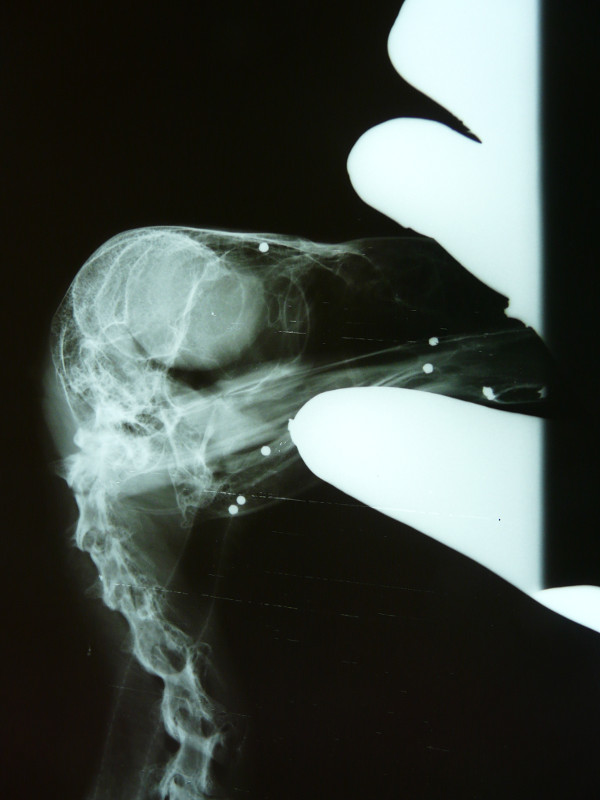

Por otro lado, y con mucha peor suerte, el domingo 11 de Noviembre ingresaba el ejemplar de buitre negro con signos de traumatismo, débil y deprimido, apenas se ponía en pie y tenía un ala descolgada. Se diagnosticó una fractura de radio y luxación de codo, pero su estado era tan grave que se decidió esperar 24 horas para realizar la radiografía, en la que encontramos más de 25 perdigones distribuidos por todo el lateral derecho del cuerpo y algunos dentro de la cavidad corporal y en la cabeza, confirmando además nuestros peores temores: había fractura también de húmero a nivel del codo, lo que hacía que este ejemplar de buitre negro ya apuntara como irrecuperable para el resto de sus días. El desplazamiento de los fragmentos en la zona de la articulación del codo había provocado una inflamación gravísima en la zona y destrucción de los tejidos blandos (musculatura, cápsula articular, ligamentos) y empezaba a haber pérdida de sensibilidad y fallo vascular en la parte más distal del ala.

Decidimos intervenir quirúrgicamente el pasado miércoles viendo que la inflamación del codo iba cada vez a peor y que el animal estaba dejando de comer por el dolor y las molestias. Durante la cirugía pudimos comprobar que la vena cubital había sido dañada por los fragmentos de hueso y se había producido una acumulación severa de líquido, además de inicio de necrosis de algunos músculos y tendones.

La tremenda decisión que tuvimos que tomar fue la de amputar el ala a nivel del húmero distal (para conservar la mayor longitud de ala posible). Tras 4 largas horas de cirugía, el animal despertó y hoy está comiendo bien de nuevo aunque aún adaptándose a la pérdida de un ala casi completa. Su futuro será pasar a formar parte del núcleo reproductor de GREFA, sabiendo que nunca más podrá volver a volar y pasar el resto de su vida en las mejores condiciones posibles pero en cautividad.